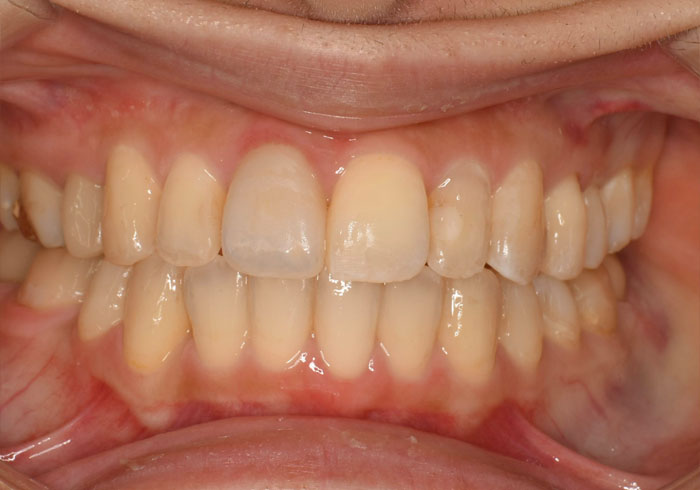

治療後

マウスピース矯正 マウスピース矯正 マウスピース矯正

もともと右上前から4番目の歯が1本欠損しており、左右のバランスを合わせるために右下の歯を1本抜歯して治療を行いました。

必ずしも歯を抜かないと矯正治療ができないというわけではありませんが「笑顔やお顔とのバランス」を考慮し、今回は抜歯を提案させていただきました。